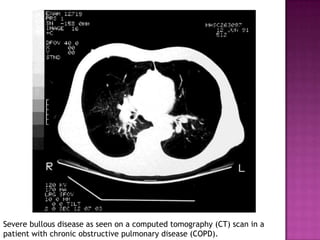

A computed tomography (CT) scan shows hyperlucency due to diffuse

hypovascularity and bullae formation, predominantly in the upper lobes.

Severe bullous disease as seen on a computed tomography (CT) scan in a

patient with chronic obstructive pulmonary disease (COPD).